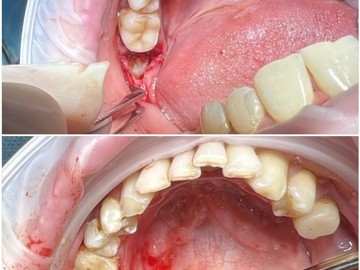

Атравматичное удаление зубов – наиболее безболезненная и щадящая процедура, которая практически не травмирует десну и костную ткань.

Зуб извлекается частями, что позволяет не травмировать окружающие ткани.

В нашей клинике осуществляется удаление самых сложных «зубов мудрости». Обычно удаление зуба под местной анестезией занимает от 10-15 минут, но иногда процедура может занять 30 или даже 60 минут и более.